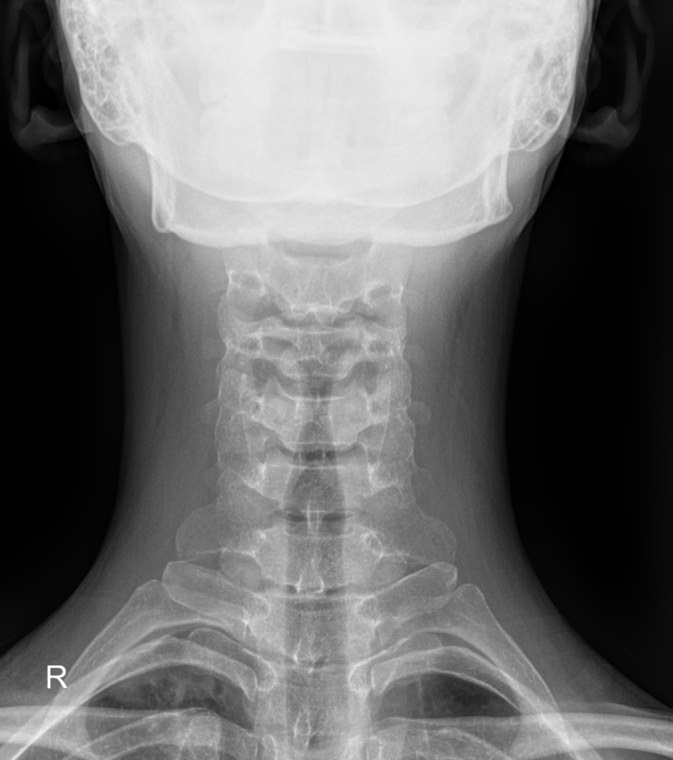

Как и другие кости, шейные позвонки отлично визуализируются с помощью рентгена. На снимках отчетливо видны признаки острых и хронических патологий, а часть врожденных аномалий обнаруживается случайно именно на рентгенограммах. В снимок попадают средние и нижние шейные, а также 2-3 верхних грудных позвонка. Для исследования двух верхних позвонков требуется специальная  проекция ― «через открытый рот».

Снимки могут быть назначены в 2 и более проекциях, которые указаны в направлении:

• Прямой ― лежа на спине с чуть запрокинутой головой;

• Боковой ― чаще стоя или сидя боком к пластине детектора;

• Косой ― тоже стоя или сидя, повернувшись к пластине на 30-45о.